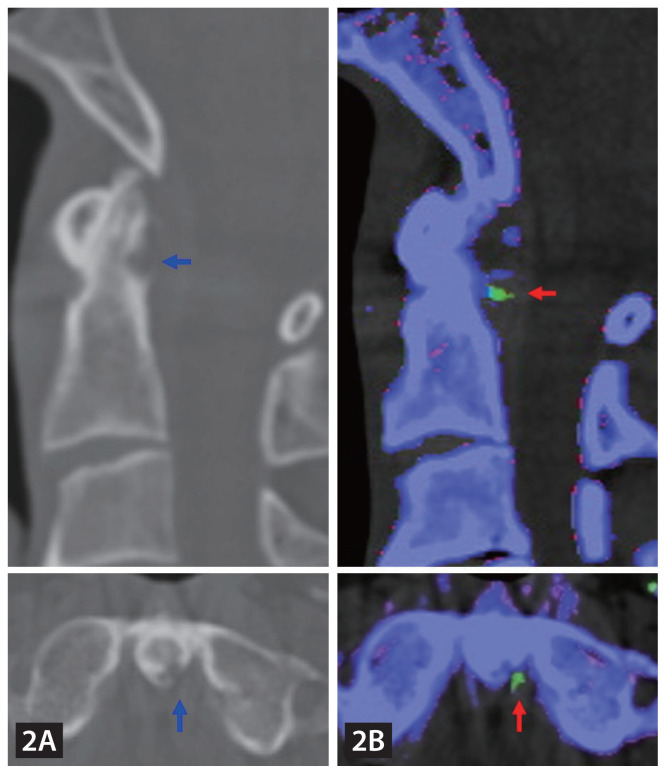

寰枢关节急性痛风性关节炎。

Acute gouty arthritis of the atlantoaxial joint.